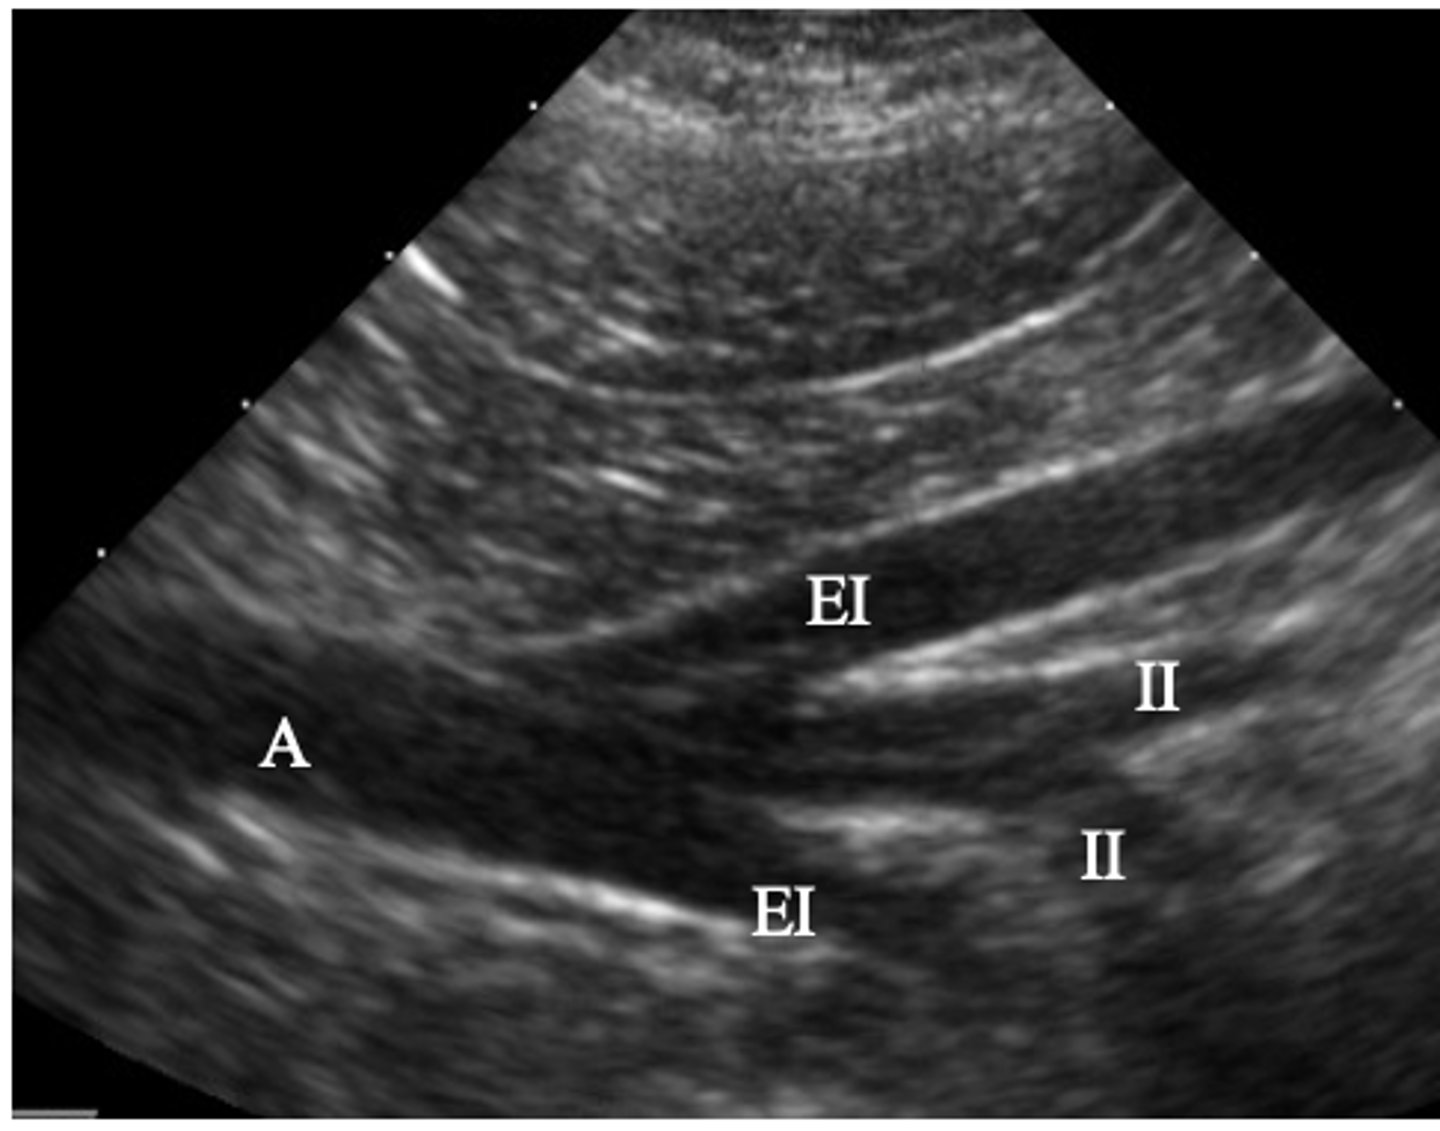

A- aorta

EI- external iliac artery

II- internal iliac artery

ID vasculature on US